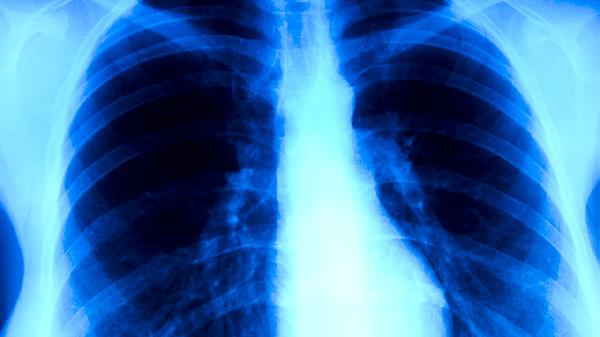

肺結核的癥狀主要有咳嗽、咳痰、咯血、胸痛、發(fā)熱等。肺結核是由結核分枝桿菌感染引起的慢性傳染病,主要通過呼吸道傳播,建議患者及時就醫(yī)。

肺結核患者通常會出現持續(xù)咳嗽的癥狀,咳嗽時間較長,可能超過兩周??人猿跗诙酁楦煽龋S著病情發(fā)展可能出現咳痰。咳嗽可能與結核分枝桿菌感染肺部組織,導致炎癥反應有關?;颊呖勺襻t(yī)囑使用異煙肼片、利福平膠囊、吡嗪酰胺片等抗結核藥物進行治療。

肺結核患者咳出的痰液多為白色黏液痰,病情嚴重時可能出現黃綠色膿性痰。部分患者痰中可能帶有血絲,這與肺部組織受到結核分枝桿菌破壞有關?;颊咝枳⒁獗3趾粑劳〞?,避免痰液堵塞氣道,可遵醫(yī)囑使用鹽酸乙胺丁醇片、鏈霉素注射液等藥物。

肺結核患者可能出現咯血癥狀,表現為痰中帶血或大量咯血。咯血通常與肺部血管受到結核病灶侵蝕有關,嚴重時可能導致窒息?;颊叱霈F咯血時應立即就醫(yī),醫(yī)生可能會建議使用止血藥物如氨甲環(huán)酸注射液,同時繼續(xù)抗結核治療。

肺結核患者常感到胸部隱痛或刺痛,疼痛多在咳嗽或深呼吸時加重。胸痛可能與胸膜受到結核分枝桿菌感染有關,也可能由肺部炎癥刺激胸膜導致?;颊呖勺襻t(yī)囑使用對乙酰氨基酚片緩解疼痛,同時繼續(xù)規(guī)范的抗結核治療。

肺結核患者通常會出現午后低熱,體溫多在37.5-38.5攝氏度之間,可能伴有盜汗、乏力等癥狀。發(fā)熱是機體對結核分枝桿菌感染的免疫反應,隨著抗結核治療的有效進行,發(fā)熱癥狀會逐漸緩解?;颊邞⒁庑菹ⅲa充營養(yǎng),增強免疫力。